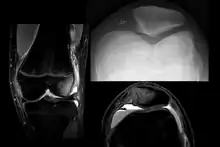

X-ray and MRI after luxation of the patella. There is a fragment and bone bruise at the medial surface of the patella and in the corresponding surface of the lateral condyle of the femur. The medial retinaculum of the patella is disrupted.